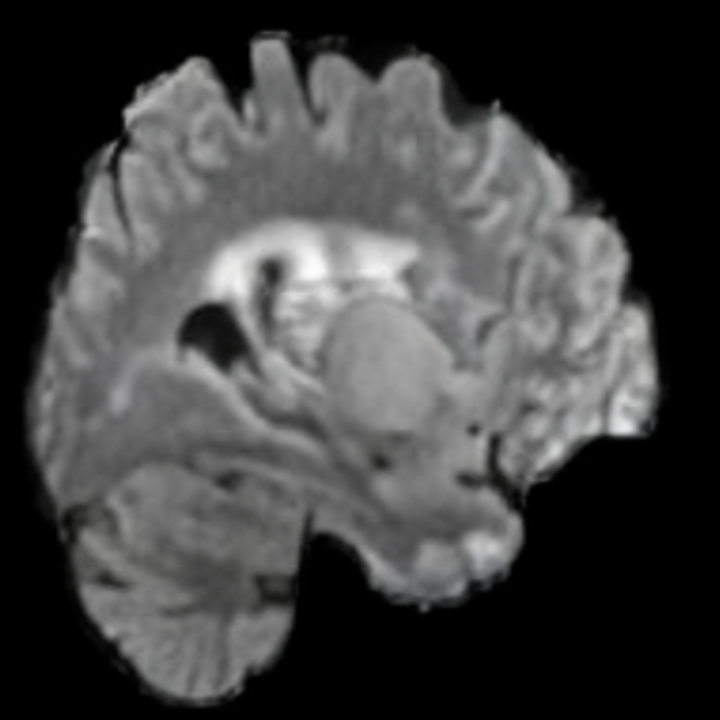

Our results unequivocally highlight the superior performance of X-Diffusion in terms of both qualitative and quantitative metrics. Representative MRI volumes generated by our pipeline, when juxtaposed with ground-truth images, showcased remarkable similarity, with even intricate physiological features like tumor information, spine curvature, and fat distribution being accurately captured.

Notably, X-Diffusion achieves sota dB for a few input slices while baselines require more than 60 input slices to achieve similar performance (Figure 7). The margin is more than 12 dB PSNR for the 1-slice input in both the BRATS and the UK Biobank benchmarks (see Table 1 and Figure 6). For reference, two randomly sampled MRIs from the UK Biobank would have a PSNR of 15.95 dB 0.36 (on 4800 randomly sampled examples). The slices from 3D reconstructed volumes at varying depths and axis of rotation visually match the ground truths (see Figures 5 and Figure 4). We also plot the error map (Figure 4) of such X-Diffusion generations to highlight the differences with the ground truth MRIs.